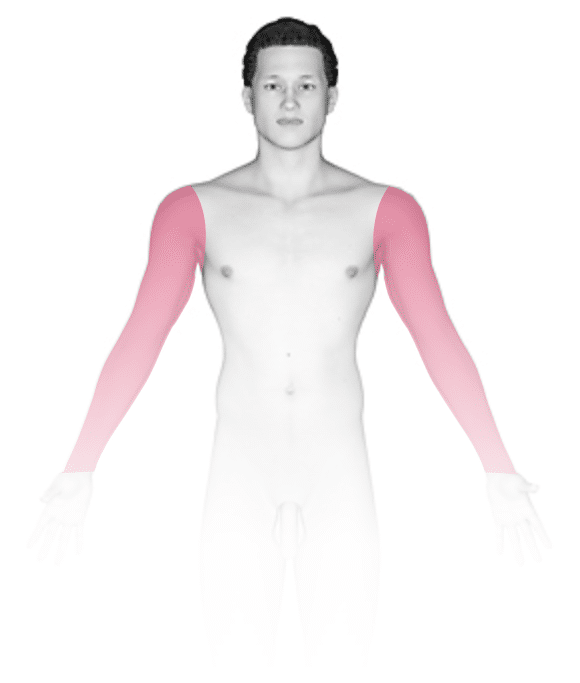

Onychomycosis, commonly known as fungal nail infection, is an infection of the fingernails or toenails by forms of fungi and yeast. Fungal nail infection accounts for nearly half of all nail disorders. In the most common form of fungal nail infection, fungus grows under the growing portion of the nail (hyponychium) and spreads up the finger toward the nail origin (proximally) along the nail bed and the grooves on the sides of the nails. A less common type of fungal nail infection may occur in patients with HIV/AIDS.

- In general, toenails are most commonly affected with fungal nail infections. If the fingernails are affected, the toenails are usually affected as well. Nails often become thicker and lift from the nail bed (onycholysis) starting at the growing portion of the nail. You might then see debris under the nails and discoloration of the affected area.

- In fungal nail infection, one, a few, or all nails may be affected.